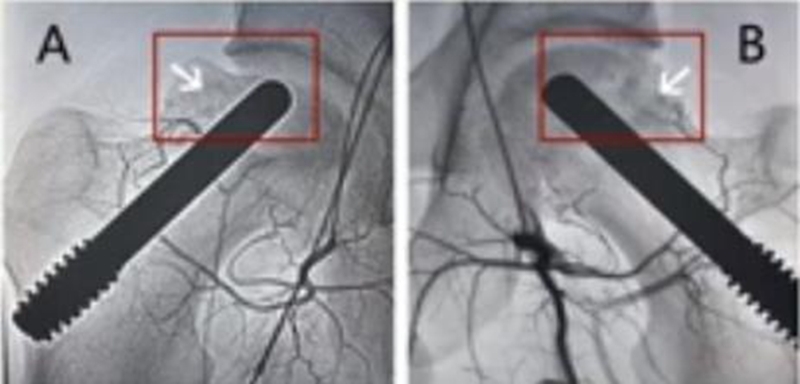

5、髓芯减压联合钽棒植入术

此方法最早由Pedersen提出,直到2005年多孔棒材料才广泛运用到临床研究中,浙江省中医院团队于2009年报告棒植入治疗早期股骨头坏死。一项138髋采取钽棒治疗,平均4年随访时间发现43例(31%)需再次实行髋关节置换术。Tsao在一项长达4年的研究中发现,19个关节(113)进行了再次的THA手术。Floerkemeier报道,在手术平均1.45年后,13例(23)需要再次THA手术,其结论是髓芯减压联合钽棒植入疗效不比单纯髓芯减压好。